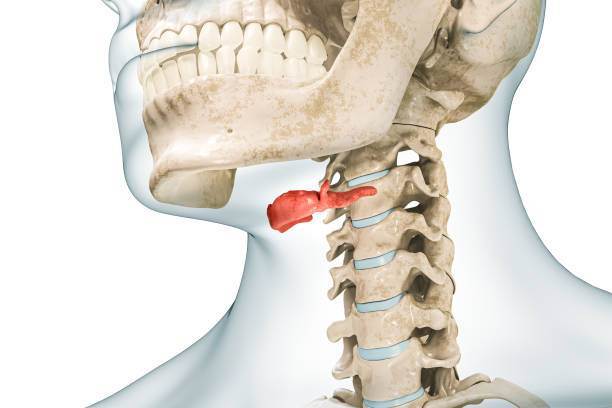

АнтонТЛТ Опубликовано 4 марта, 2024 Поделиться Опубликовано 4 марта, 2024 Ничего странного на снимке не вижу. Возможно есть гипертонус жевательной мышцы в этой области. То что белое на снимке, это наложение подъязычной кости. 2 Ссылка на комментарий